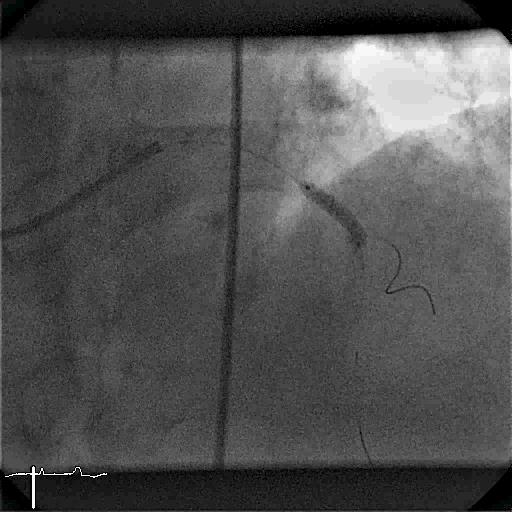

Druckdrahtmessung

Die Abbildung zeigt die beiden simultan durchgeführten Druckmessungen in der Hauptschlagader (Aorta = rote Linie) und am Draht in der Herzkranzarterie (grüne Linie). Der Quotient aus beiden Druckwerten (Druck grün : Druck rot) ergibt die sogenannte „Fraktionelle Flussreserve“ (FFR), die gelb dargestellt ist. Es ist der Verlauf der Druckmessung während des Rückzugs des Drahts von peripher zurück bis zum Abgang aus der Aorta dargestellt. Die deutliche Änderung des am Draht gemessenen Drucks (grüne Linie) auf kurzer Rückzugsstrecke zeigt eine hochgradige Stenose an. Eine Linderung von Brustbeschwerden durch eine Stentimplantation ist in diesem Fall sehr wahrscheinlich.

Nur wenn eine umschriebene Stenose für den Druckunterschied verantwortlich ist, kann eine Implantation eines Stents in der Stenose die Durchblutung verbessern und dem Patienten die Beschwerden lindern. Wir führen die intrakoronare Druckdrahtmessung in der Asklepios Klinik in Langen zur Klärung unklarer Befunde nach Koronarangiographie durch.